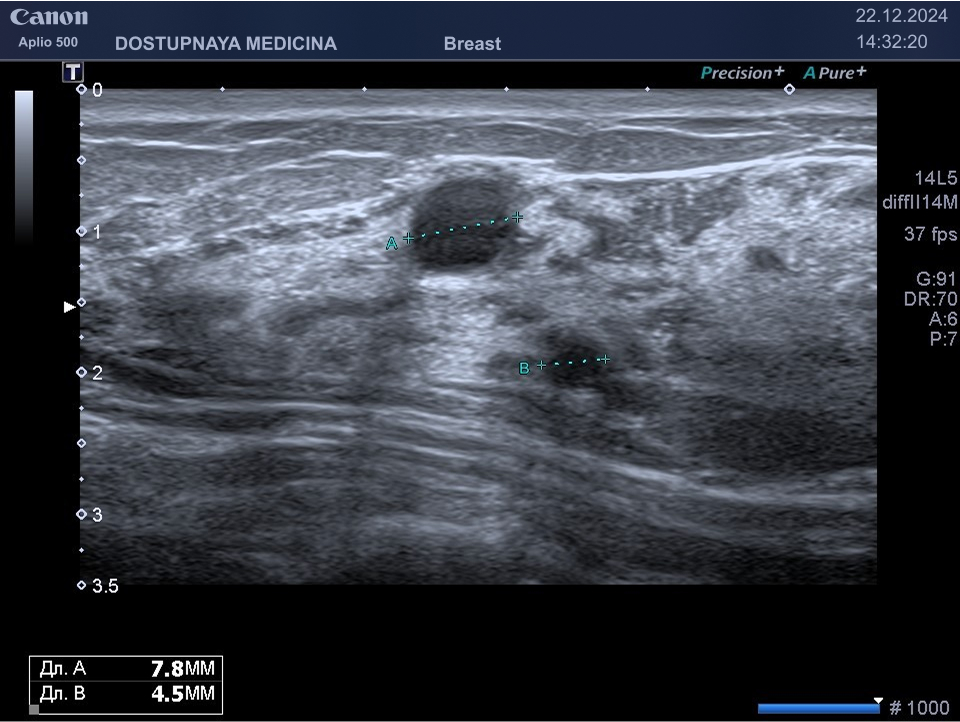

Следует проводить дифференциальную диагностику фиброаденомы с раком молочной железы, с кистой и с цистаденопапилломой. Поэтому важно повторить ультразвуковое исследование через 3 месяца, а затем при отсутствии тенденции к росту опухоли необходим УЗИ контроль через 6 месяцев.

Киста молочной железы – это самое часто выявляемое образование в молочной железе во время ультразвукового исследования. Представляет собой тонкостенную полость, заполненную жидкостью.

Киста может быть заполнена жидким или густым секретом. Киста с жидким секретом на УЗИ выглядит как анэхогенное (чёрное) образование округлой или овальной формы, киста с густым секретом на УЗИ выглядит как гипоэхогенное (серое) образование.

Встречаются атипичные кисты, содержащие перегородки и имеющие неправильную форму. Такие кисты имеют большую степень онкологической настороженности и относятся к категории BI-RADS3, соответственно требуют более тщательного наблюдения.